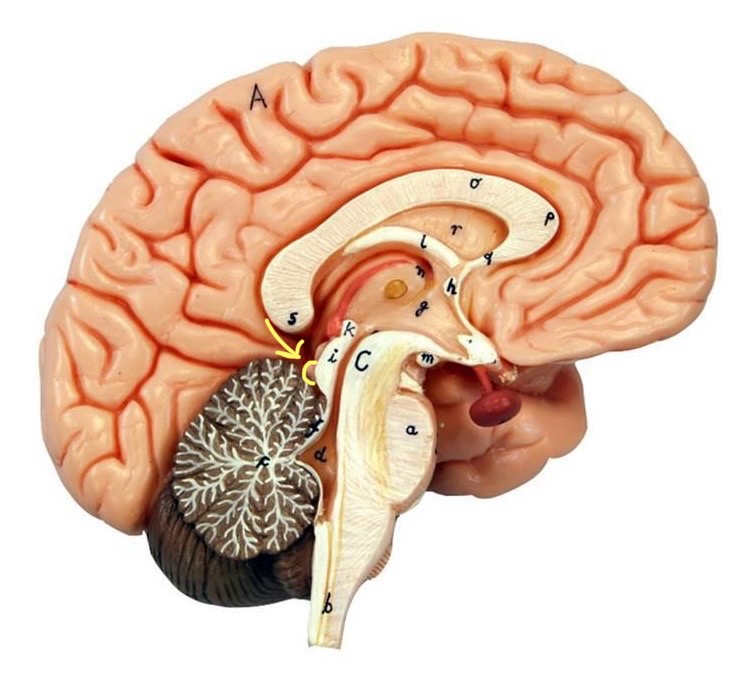

What is D?

lateral ventricle

Imagine thin membrane separating the 2 lateral ventricles

septum pellucidum

What is C?

3rd ventricle

What is B?

cerebral aqueduct

What is A?

4th ventricle

What is below A at the very end?

central canal (spinal cord)

What is C?

midbrain

tectum (corpora quadrigemina): superior colliculus

tectum (corpora quadrigemina): inferior colliculus

What is a?

pons

medulla oblongata

intermediate mass of thalamus

hypothalamus

What is the pink bulb?

pineal gland

corpus callosum

fornix

What is A?

cerebral cortex

cerebral tracts

cerebral hemispheres

longitudinal fissure

What are these ridges?

gyri

What are these shallow grooves?

sulci

Divides parietal from frontal lobe

central sulcus

precentral gyrus

postcentral gyrus